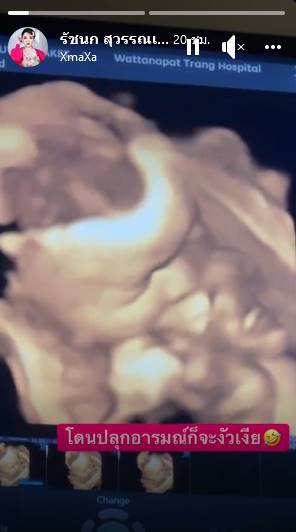

เจนนี่ ได้หมดถ้าสดชื่น เผยภาพอัลตราซาวด์ลูกสาวในท้อง ดูแค่นี้รู้เลยลูกใคร ยิว ฉัตรมงคล คลั่งรักหนักตื่นเต้นอีก 1 เดือนได้เจอกันแล้ว